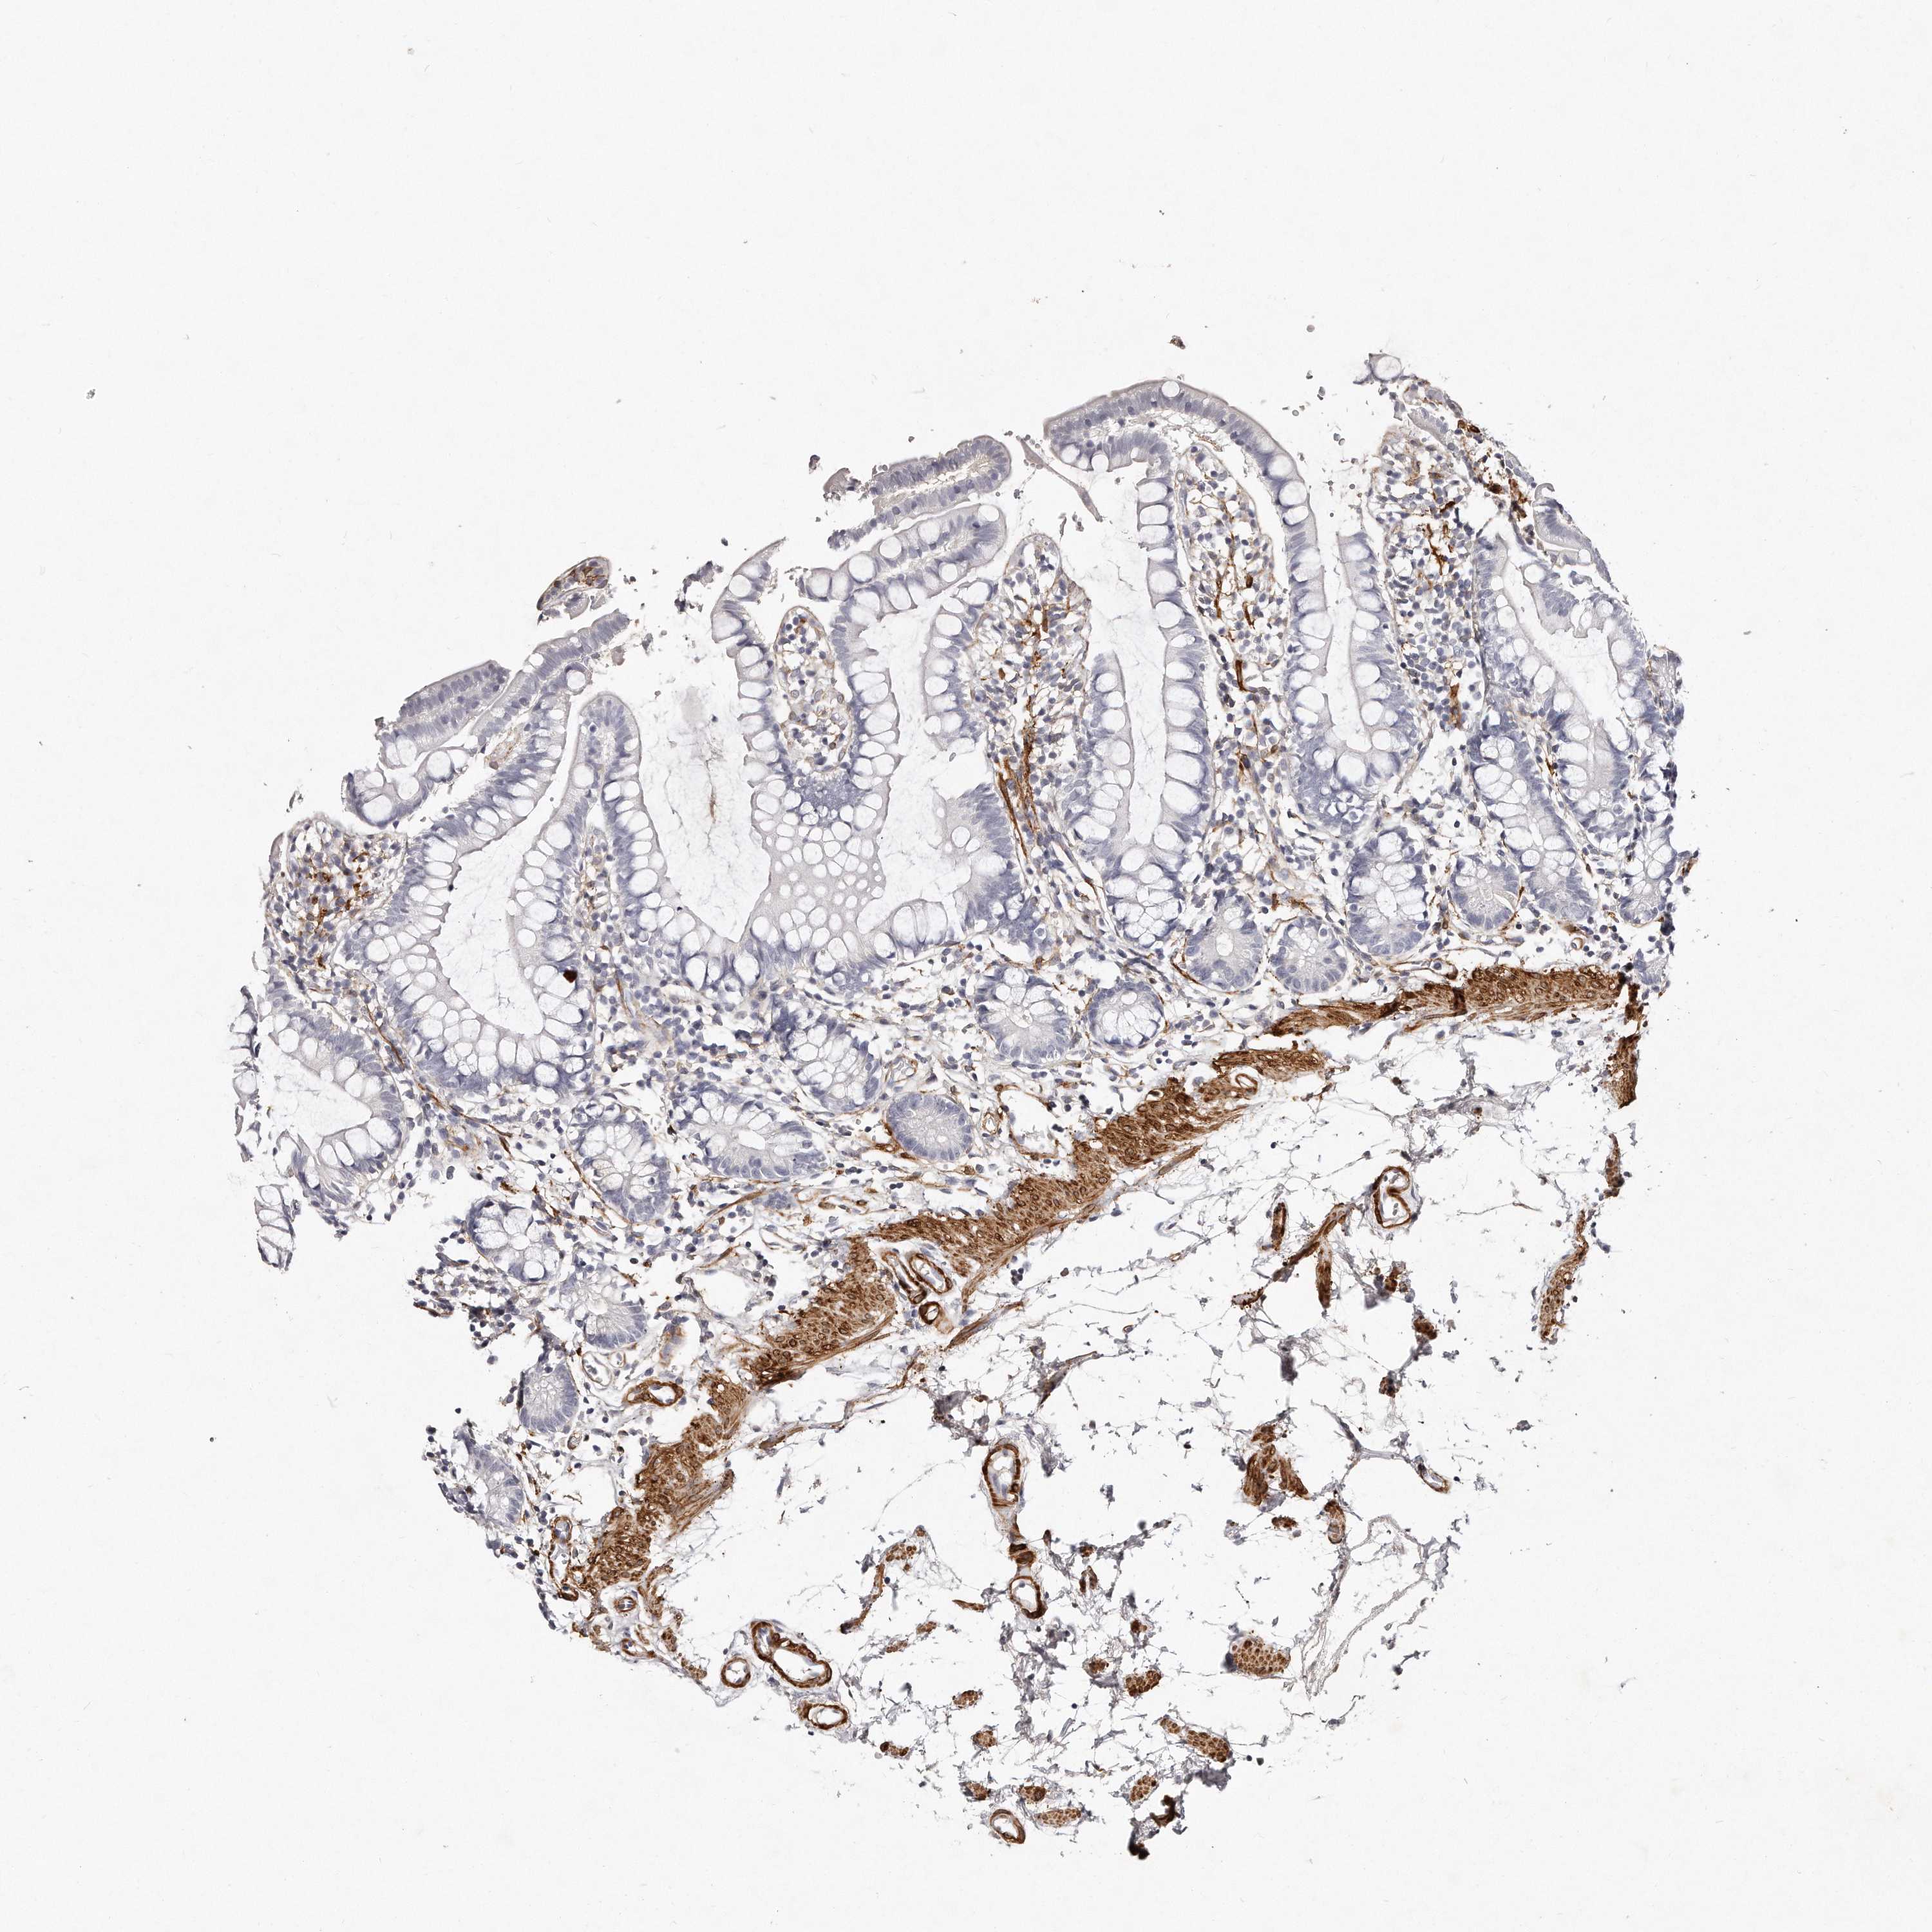

SMALL INTESTINE - Antibody stainingi

Antibody staining in the annotated cell types in the current human tissue is reported as not detected, low, medium, or high, based on conventional immunohistochemistry profiling in selected tissues. This score is based on the combination of the staining intensity and fraction of stained cells.

Each image is clickable and will lead to virtual microscopy that enables deeper exploration of all samples and also displays staining intensity scores, fraction scores and subcellular localization as well as patient and tissue information for each sample.

Antibody HPA028325Antibody HPA028435Antibody HPA030097

Glandular cells Not detectedNot detectedNot detected